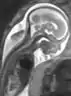

Fetal therapy, or fetal treatment, is part of fetal medicine. It includes interventions performed on a “sick” fetus with the aim of achieving fetal well being. These interventions include medical (i.e. non-invasive) and surgical procedures. In general a medical intervention is performed by administering medication to the mother. The drug crosses through the placenta and reaches the blood circulation of the fetus. Surgical intervention on the fetus may involve either a direct operation of the fetus or an intervention on the placenta, as in the case of twin-twin-transfusion syndrome (TTTS). In some cases, it may be performed at the time of delivery: the Ex Utero-Intrapartum (“EXIT procedure”) procedure.